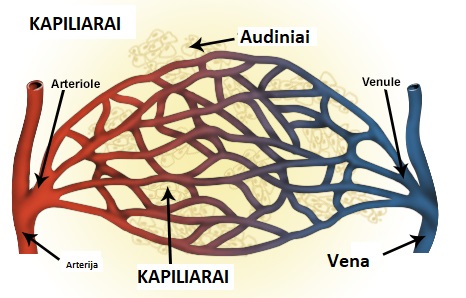

2. Kraujotakos sutrikimai

- Sumažėjusi kraujotaka į vidinės ausies struktūras gali lemti garsinės informacijos perdavimo sutrikimus.

- Venų stazė galvos srityje, atsirandanti dėl kaklo kraujagyslių suspaudimo, gali sukelti pulsuojantį tinitą.

3. Kraujotakos sutrikimai – „pulsuojantis tinitas“

- Esant kraujotakos sutrikimams galvos srityje, dažnai pasireiškia pulsuojantis ūžesys, kuris sinchronizuojasi su širdies ritmu.

- Venų stazė (užsikimšusios arba neefektyviai dirbančios kraujagyslės).

- Padidėjęs kraujospūdis, sukeliantis vidinės ausies kraujotakos pokyčius.

- Slankstelinės arterijos suspaudimas dėl laikysenos ar raumenų įtampos.

2. Kraujotakos gerinimo poveikis tinitui

- 2020 m. atliktas tyrimas (Cagnie et al.) įrodė, kad manualinė terapija kartu su kraujotaką gerinančiais metodais (pvz., miofascialiniu atpalaidavimu) pagerino vidinės ausies kraujotaką ir sumažino tinitą 72 % pacientų.

- Geresnis kraujo pritekėjimas į slankstelines arterijas leido sumažinti pulsaciją ir pagerinti klausos sistemos funkciją.